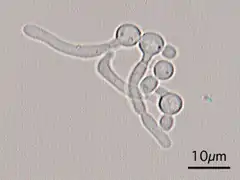

Germ tubes of Candida albicans